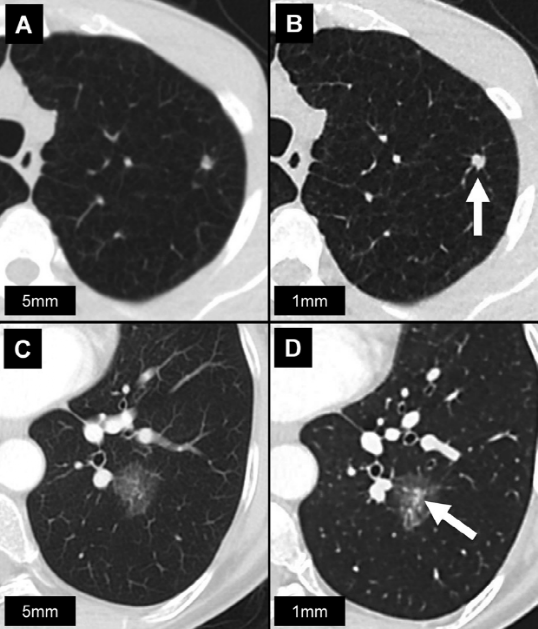

左肺上叶A、B,实性结节 (箭头)。左肺下叶C、D,亚实性结节 (箭头)。

与B和D相比,由于部分容积效应,A和C上的实性和亚实性结节边界显示较差。此外,D更好地显示出结节的实性成分。